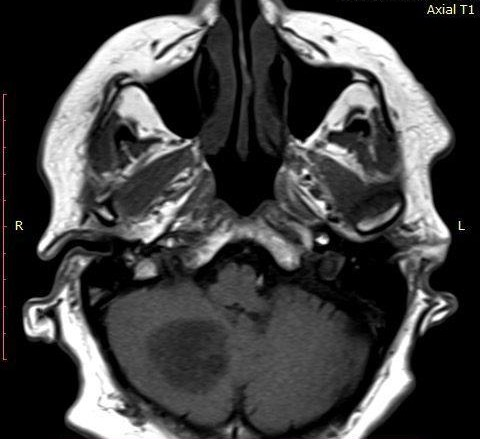

A ressonância magnética de crânio evidenciou grande lesão sólido-cística no corpo medular do cerebelo à direita, com efeito expansivo significativo (Figura 1).

A lesão, com dimensões 30,9x32,0x36,4, apresentou hipersinal em T2 (Figura 2) e FLAIR (Figura 3), hipossinal em T2, depósitos de hemossiderina nas bordas, área de restrição à difusão e intenso realce pós-contraste na porção sólida. As áreas císticas sugerem alto grau de necrose.

Figura 1. Ressonância magnética de crânio axial T1